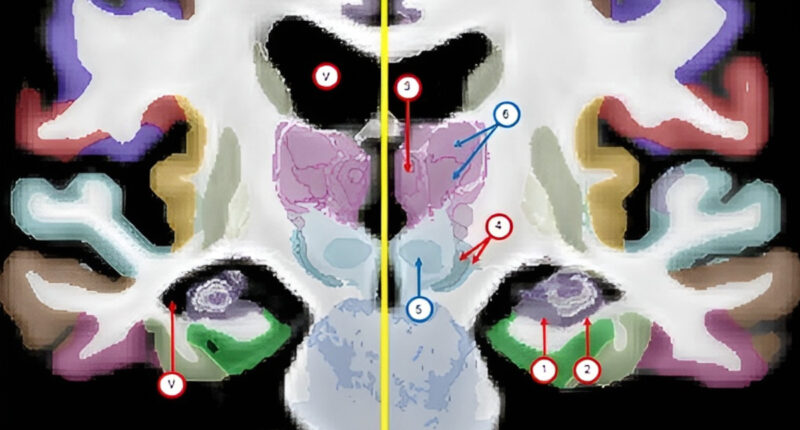

The atlas, called NextBrain, took the research team six years to build through a painstaking process using post-mortem tissue from five human brains. Each brain was dissected and sectioned into 10,000 pieces, stained to help identify brain structures, photographed under a microscope, and then reassembled into a 3D digital model.

AI was used to help align the microscope images and the MRI scans, accounting for the differences between the two techniques and ensuring that the pieces did not overlap or have gaps in between them. A total of 333 brain regions were then labelled on the digital 3D models of each of the five brains, a process greatly accelerated by AI that would have taken decades if done manually.

The resulting atlas, which is an average of the five brain models, is generalisable to all adult humans, meaning it can be used to automatically infer details from MRI scans of living or deceased subjects.